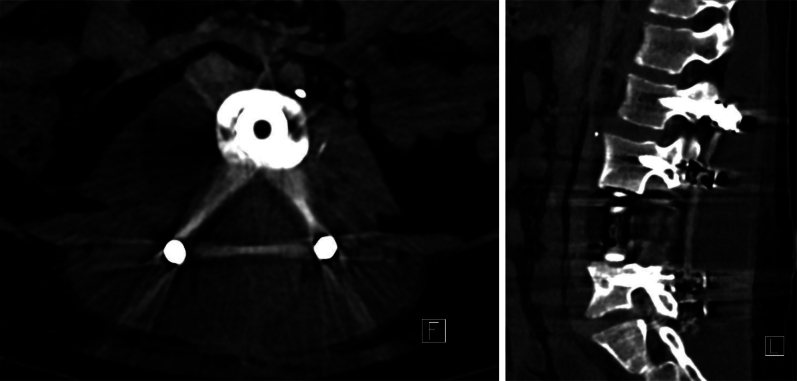

Observations: The authors present the first documented case of planned division and mobilization of the vena cava supported by venous-venous bypass in order to achieve gross-total resection of a lower lumbar malignant peripheral nerve sheathe tumor as part of a two-stage procedure.

Lessons: Inferior vena cava division and reanastomosis is a novel technique that can be used to widen surgical corridors in anterior approaches to the lumbar spine, and one that proves useful in en bloc resections. Venous-venous bypass can minimize impact on right heart filling during prolonged surgery. https://thejns.org/doi/10.3171/CASE25151.